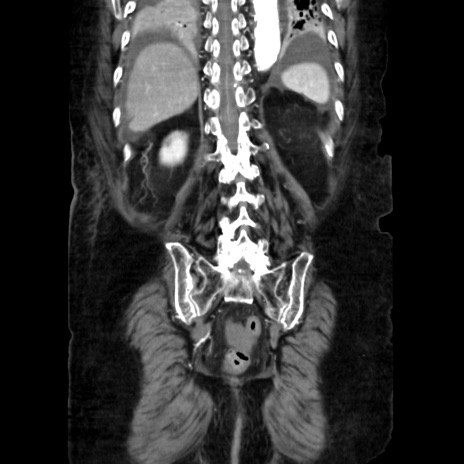

症例40(冠状断像)

【症例】90歳代女性

【主訴】腹痛・嘔吐

【現病歴】 食欲低下、嘔吐があり昨日他院受診。肺炎と診断され入院となる。入院後より腹部全体に圧痛あり。胃管留置され経過みていたが、症状持続するため、

当院転院となる。

【既往歴】胸椎圧迫骨折、胆石症

【身体所見】腹部:中央に激痛あり、圧痛あり、反跳痛不明

【データ】WBC 17100、CRP 18.82

冠状断像